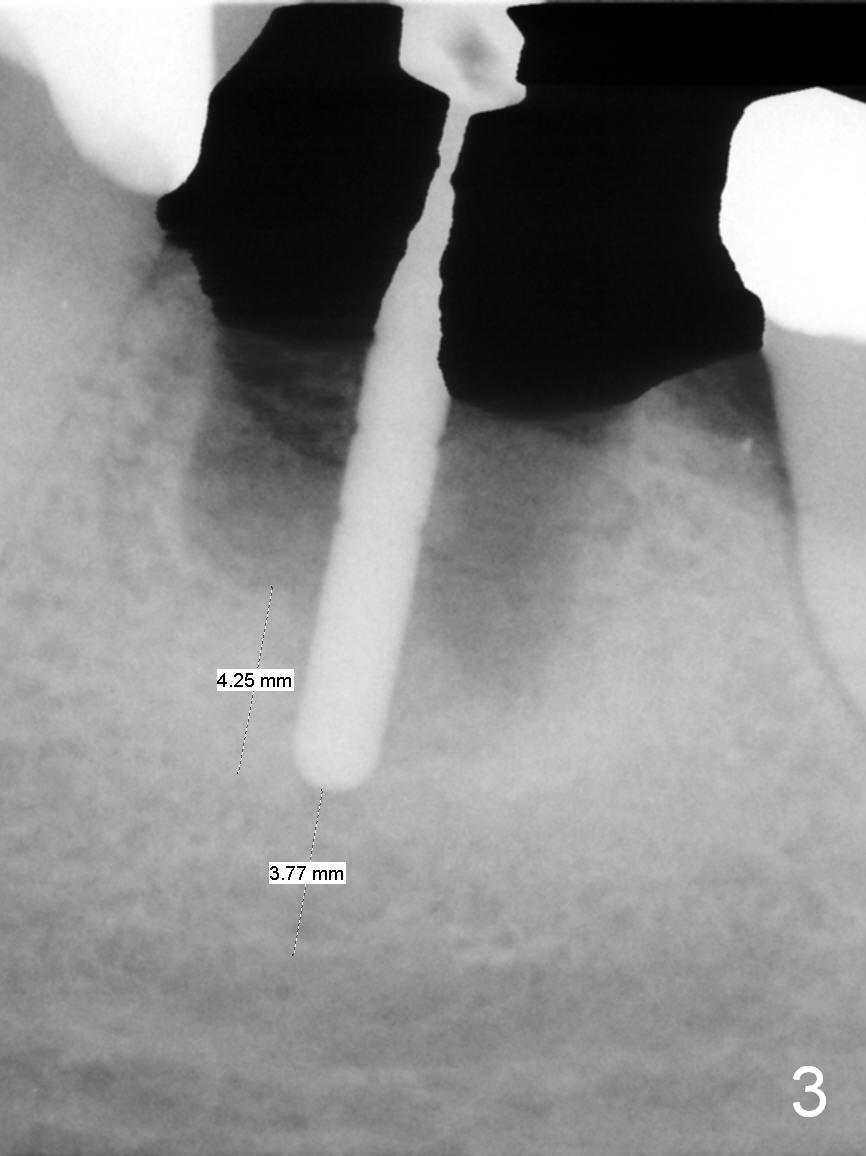

A 56-year-old lady (YW) has diabetes II, fairly well controlled. Although there is radiologic evidence of mesial root fracture of the tooth #19 (Fig.1 (panoramus)), she is asymptomatic. The buccal gingiva is slightly erythematous and edematous. There is no deep pocket. According to Fig.1, either the buccal or lingual wall is lost. This is not evident from Fig.2 (PA). Osteotomy is established in the septum or the distal socket (treated with Clindamycin), away from the lost plate (Fig.6,7). It is estimated that there is 4-5 mm apical bone. Measure the depth of the socket. Osteotomy should be 3 mm beyond the socket.